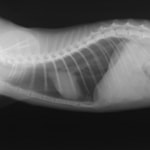

診断:胸部レントゲン検査にて、前縦隔領域に不透過性亢進領域を確認しエコー検査にてFNAを実施。細胞診の結果「低〜中分化型リンパ腫」と診断

前胸部にみられた不透過性領域の退縮が認められます